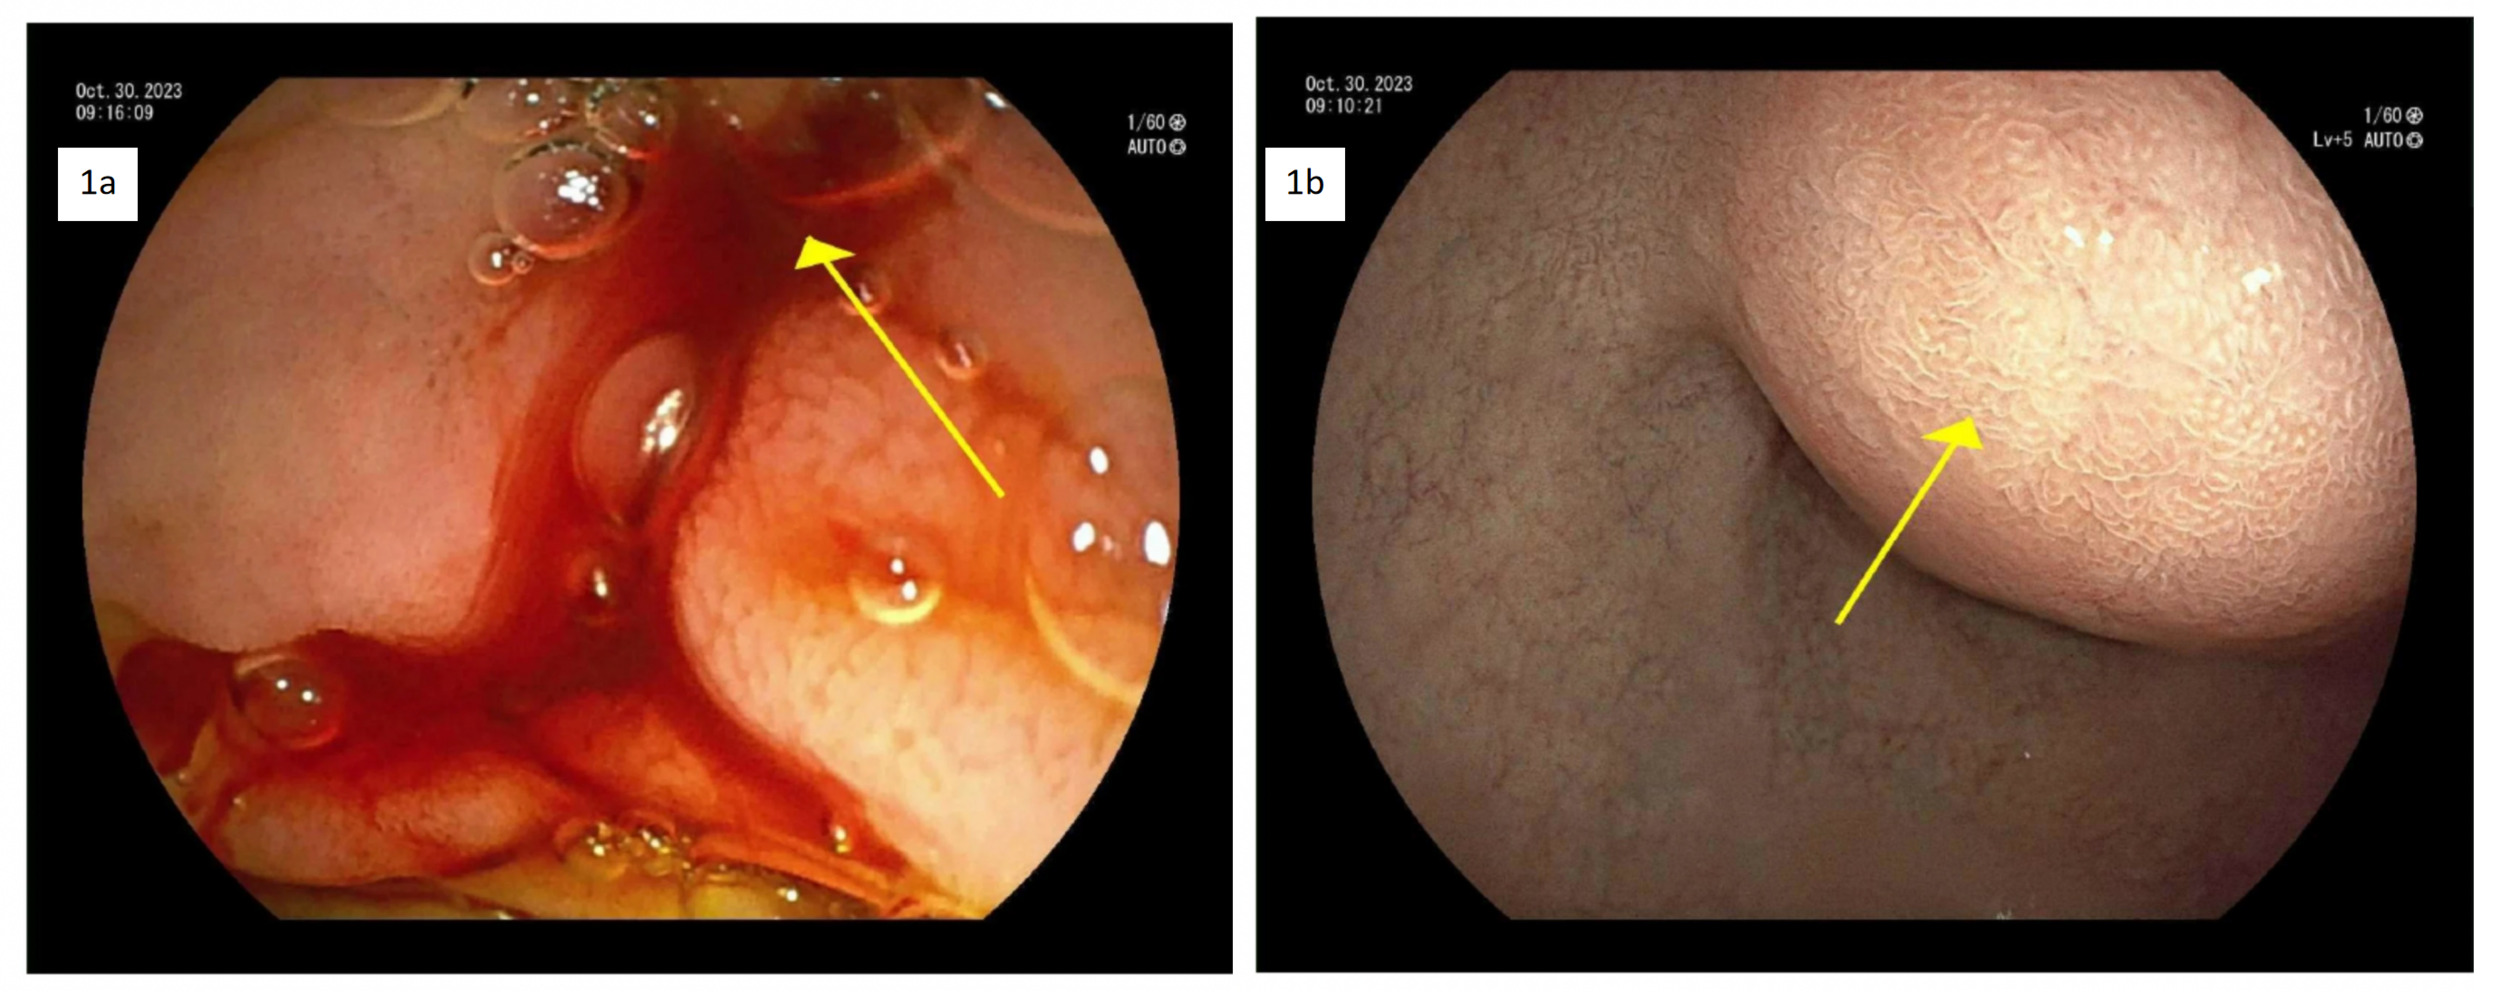

On day 2, an emergency Celiac artery angiography was performed by Interventional Radiology, which demonstrated a patent GDA with delayed and faint filling of a pseudoaneurysm centered in the GDA territory. The angiograms of the superior mesenteric artery (SMA) and the inferior pancreaticoduodenal artery (IPDA) demonstrated brisk filling of a large pseudoaneurysm in the GDA territory (Figure 2) and an additional, much smaller pseudoaneurysm more distally with a large feeding vessel from the IPDA. Subsequently, micro-catheterization of the SMA and retrograde catheterization of the proximal GDA were performed. Due to difficulties in deploying POD 6 and POD 4 coils, coil embolization was ultimately performed using multiple detachable and soft coils appropriately sized to the target vessels. Post-embolization angiography from IPDA demonstrated successful occlusion of the GDA and the large pseudoaneurysm, as well as that of large feeding vessels to the smaller pseudoaneurysm (Figure 3). A follow-up CT scan on day 3 confirmed resolution of the pseudoaneurysm and a stable hematoma.